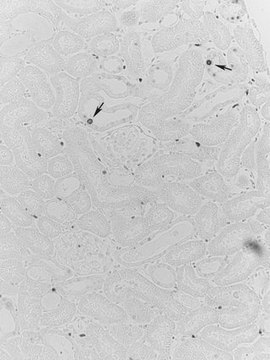

抗-PCNA抗体,克隆PC10 clone PC10, Upstate®, from mouse